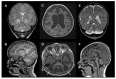

Coenzyme Q10 (CoQ10) is an endogenously synthesized lipid molecule. It is best known for its role as a cofactor within the mitochondrial respiratory chain where it functions in electron transfer and ATP synthesis. However, there are many other cellular pathways that also depend on the CoQ10 supply (redox homeostasis, ferroptosis and sulfide oxidation). The CoQ10 biosynthesis pathway consists of several enzymes, which are encoded by the nuclear DNA. The majority of these enzymes are responsible for modifications of the CoQ-head group (benzoquinone ring). Only three enzymes (PDSS1, PDSS2 and COQ2) are required for assembly and attachment of the polyisoprenoid side chain. The head-modifying enzymes may assemble into resolvable domains, representing COQ complexes. During the last two decades, numerous inborn errors in CoQ10 biosynthesis enzymes have been identified. Thus far, 11 disease genes are known (PDSS1, PDSS2, COQ2, COQ4, COQ5, COQ6, COQ7, COQ8A, COQ8B, COQ9 and HPDL). Disease onset is highly variable and ranges from the neonatal period to late adulthood. CoQ10 deficiency exerts detrimental effects on the nervous system. Potential consequences are neuronal death, neuroinflammation and cerebral gliosis. Clinical features include encephalopathy, regression, movement disorders, epilepsy and intellectual disability. Brain magnetic resonance imaging (MRI) is the most important tool for diagnostic evaluation of neurological damage in individuals with CoQ10 deficiency. However, due to the rarity of the different gene defects, information on disease manifestations within the central nervous system is scarce. This review aims to provide an overview of brain MRI patterns observed in primary CoQ10 biosynthesis disorders and to highlight disease-specific findings.